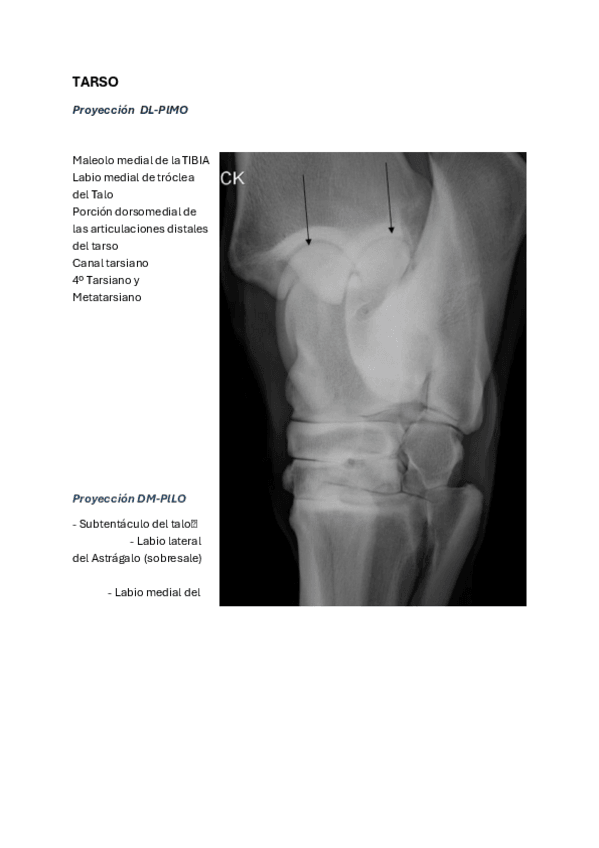

MT EQUINO

He publicado nuevos apuntes de 3º Diagnóstico Por la Imagen: MT EQUINO

Proyecciones.pdf